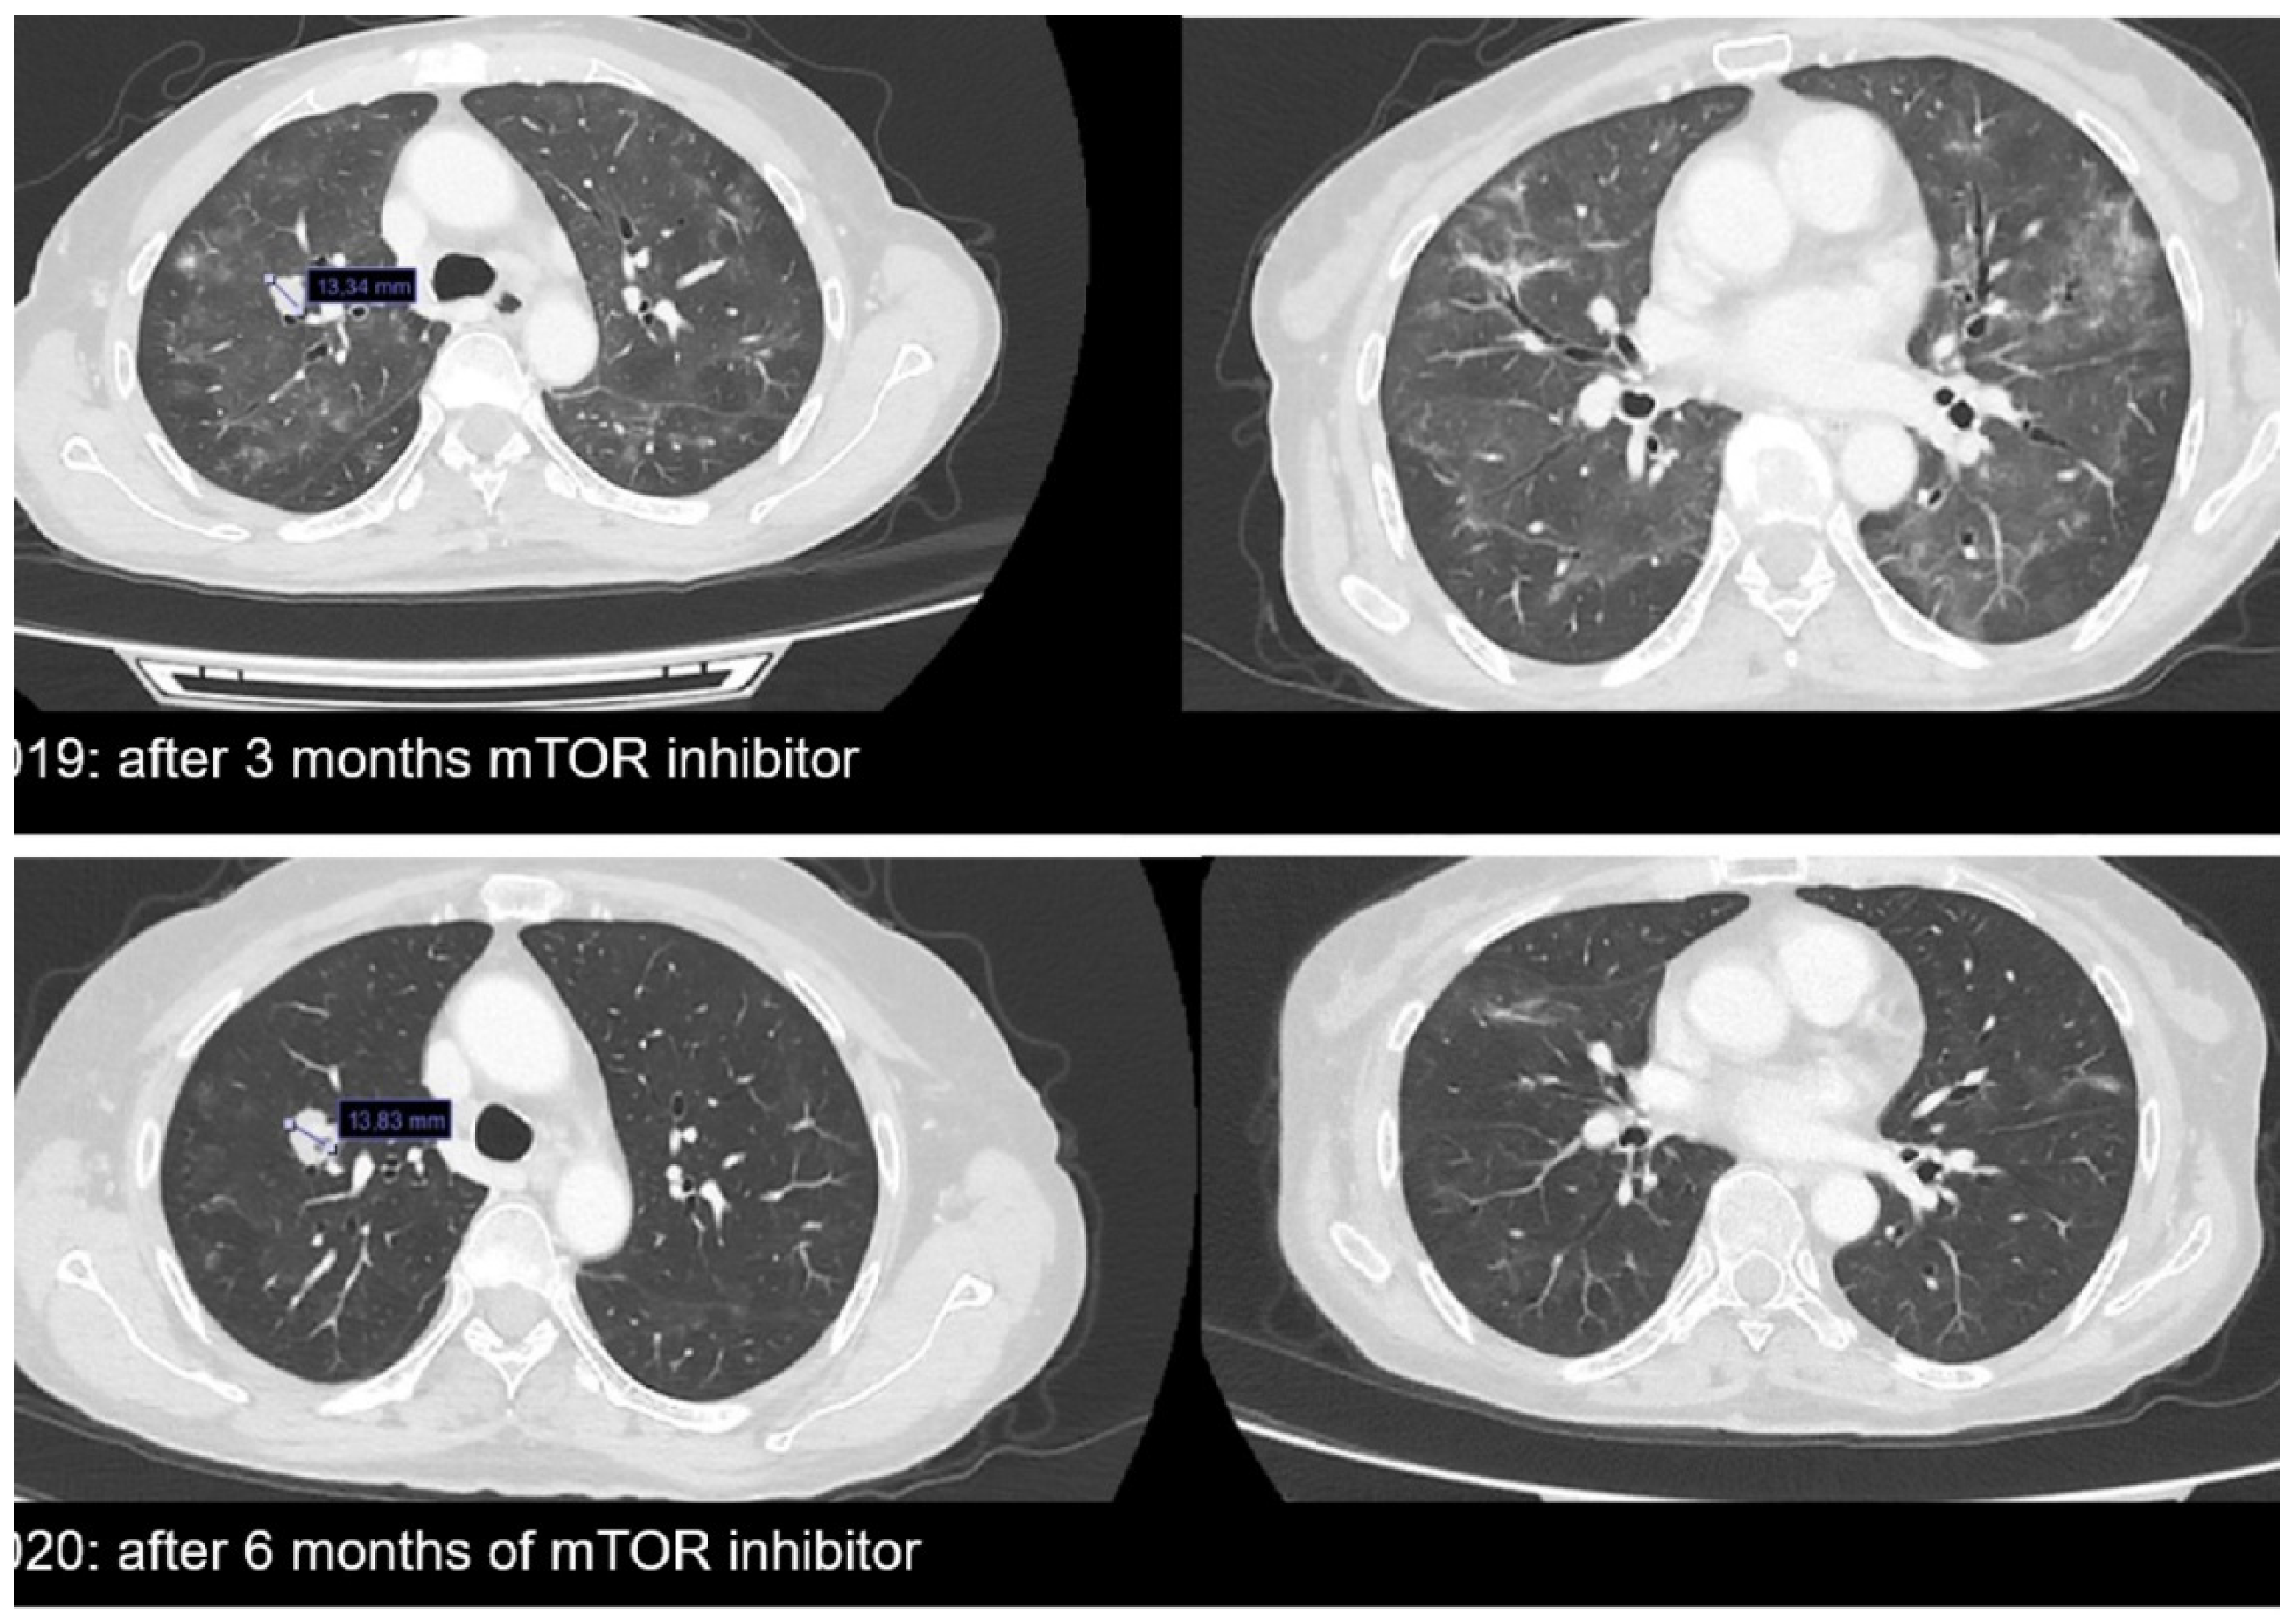

- Gluskin, J.; Plodkowski, A.; Girshman, J.; Sarasohn, D.; Viteri-Jusué, A.; Hayan, S.; Torrisi, J. Waxing and waning pattern of mTOR inhibitor-associated pneumonitis in renal cell carcinoma patients: A retrospective observational study. Clin. Imaging 2021, 71, 29–33. [Google Scholar] [CrossRef]